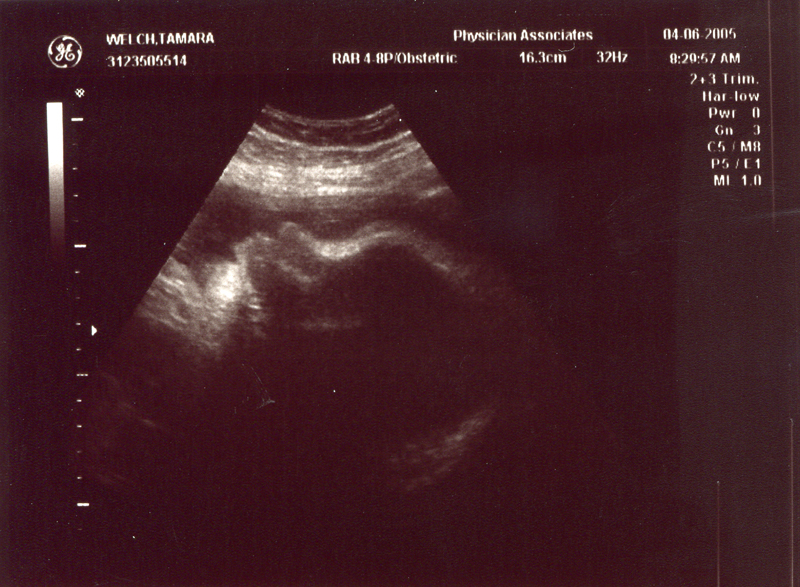

December 21, 2004 - We

had our second ultrasound and found out the sex of the baby. It's

a GIRL! We could see her moving around and see the heart beating.

We also heard the heartbeat during the doctor's visit. The heartbeat

is 150 bpm and the weight is 9 oz. Click on the images below to

see the pictures from the ultrasound. In the image titled "It's

a Girl" you can tell it's a girl because there is nothing

between the legs (the legs are in a "V" shape). We are

thrilled that everything is going well. We are planning to name

her Megan Storey Welch.